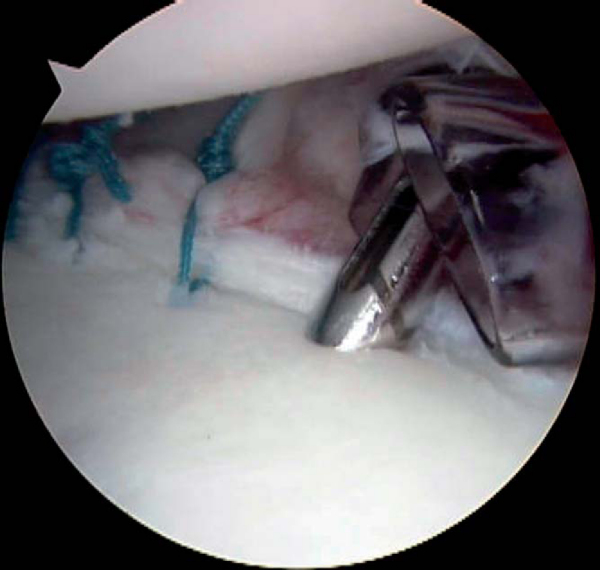

| • | Suture anchors are then placed at the articular margin of the glenoid rim, rather than down on the glenoid neck, to perform the labral repair ( Fig. 8-10 ). |

|

| • | A posterior labral tear extending from 6-o’clock to 9-o’clock on a right shoulder is typically repaired with suture anchors at the 6:30, 7:30, and 8:30 positions. | |

| • | We prefer the 3.0-mm Bio-Suture Tak suture anchor with No. 2 FiberWire (Arthrex, Inc., Naples, Fla) because of the ease of placing the anchor on the glenoid surface, but a number of other commercially available anchors are also adequate. | |

| • | The suture anchor is placed with the sutures oriented perpendicular to the glenoid rim to facilitate passage of the most posterior suture through the torn labrum. | |

| • | Avoid inadvertent injury to the articular cartilage. |